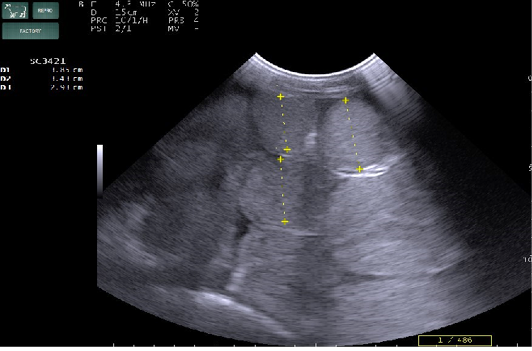

Figure 3

Percutaneous ultrasonography of right side mid abdomen showed dilated (>4.5cm) intestinal loops with mild peritonitis (Arrow).